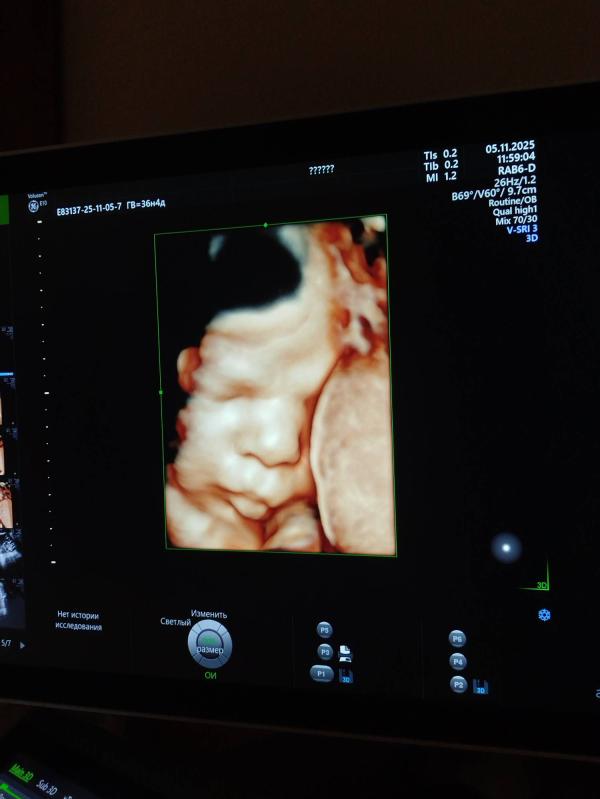

Так же ставят зрп и маловесный плод, но посмотрите на эту бусинку😍

Через 5 дней прием в жк и там решим что делать дальше. Головка прижата, но шейка длинная еще. Ходим🥸 кровотоки в идеале, в целом все хорошо, кроме ог и ож

О, эта дама с трудом далась посмотреть 🤪 сказали в следующий раз прийти на фотометрию если надо будет

Это мое первое УЗИ в 3д, я и не думала, что сделает, потому что шла на обычное😅